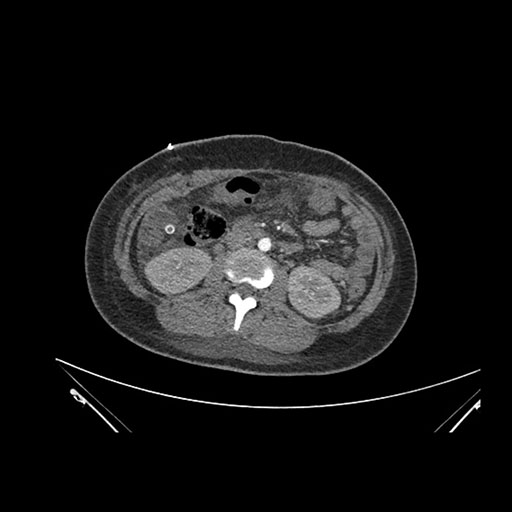

Axial Arterial

Imaging analysis

Based on initial findings, which issue(s) would you be most concerned about?